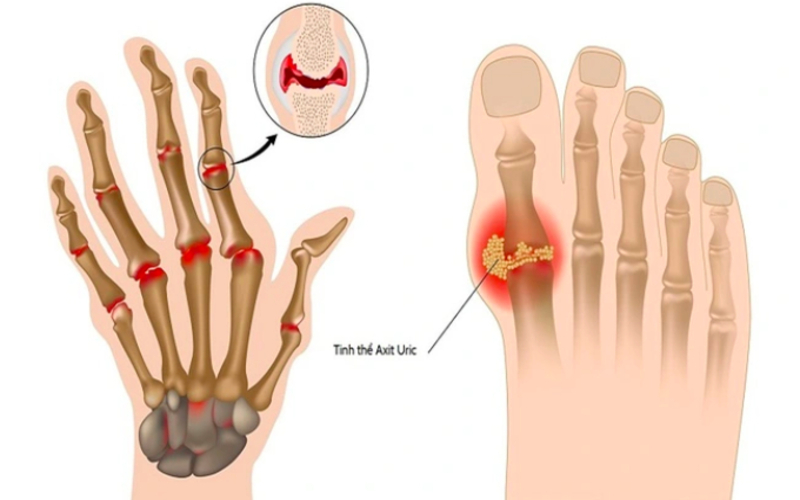

Acid uric là sản phẩm được tạo ra trong quá trình phân hủy purin – một hợp chất có nhiều trong thực phẩm như thịt đỏ, hải sản, bia rượu và cũng tồn tại tự nhiên trong tế bào của cơ thể.

Thông thường, acid uric sẽ được hòa tan trong máu và đào thải qua thận dưới dạng nước tiểu. Tuy nhiên, khi lượng acid uric vượt quá khả năng hòa tan, chúng kết tinh thành các tinh thể urat sắc nhọn, lắng đọng tại các khớp. Đây là nguyên nhân chính gây ra tình trạng viêm, sưng, đau khớp – biểu hiện đặc trưng của bệnh gout.

Khi nồng độ acid uric trong máu vượt ngưỡng 7 mg/dL, nguy cơ xuất hiện tinh thể urat tại khớp, thận và các cơ quan khác tăng cao. Điều này có thể dẫn đến nhiều biến chứng nghiêm trọng:

- Gây cơn gout cấp tính với triệu chứng đau nhức dữ dội, thường gặp ở khớp ngón chân cái.